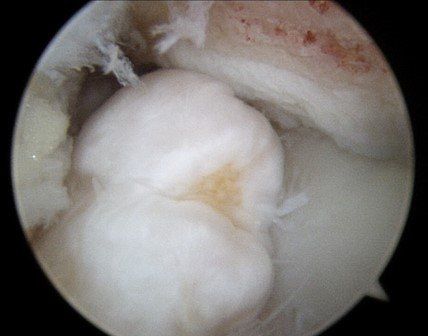

When symptoms persist, ankle arthroscopy is used to "clean-out" the ankle. Occasionally, the ankle needs to be opened to access deep scar tissue or very large spurs and bone fragments.

This procedure removes:

- scar tissue and inflammation (synovitis)

- bone spurs (see images below)

- loose bone and cartilage fragments.